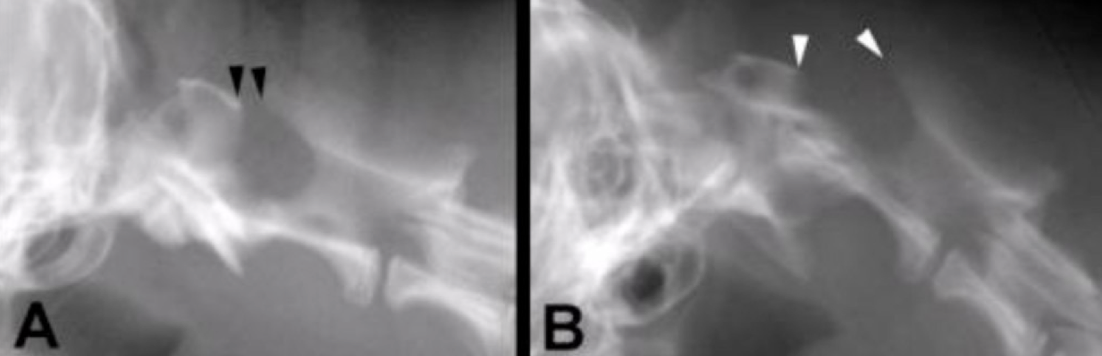

You have a dog presenting with hindlimb ataxia. It has been progressive over the past few months. You take rads and this is what you find. What is going on? How do you treat?

A

neoplasia

euthanasia, palliative, REFERRAL